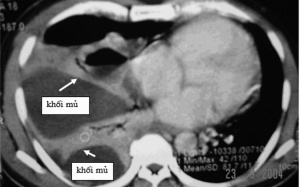

Viêm mủ màng phổi là một bệnh phức tạp, đa dạng và có thể gây nguy hiểm cho người bệnh. Viêm mủ màng phổi là hiện tượng viêm và ứ mủ trong khoang màng phổi. Nếu không phát hiện và...